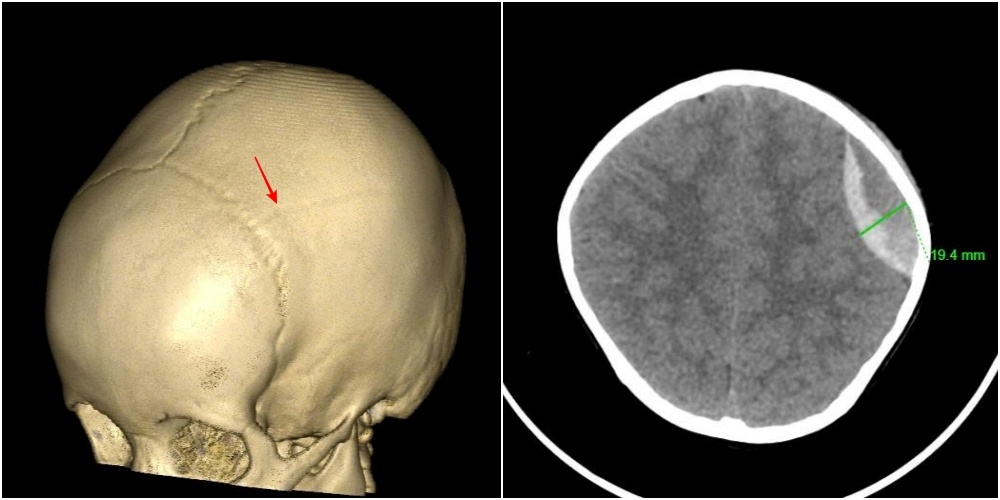

Hình ảnh vỡ xương sọ, tụ máu ngoài màng cứng đỉnh trái của bệnh nhi 3 tuổi. Ảnh: BVCC.

Trước đó một ngày, bé bị ngã trong lúc chơi nhưng vẫn tỉnh táo, vui vẻ nên gia đình chủ quan không đưa đi khám. Đến hôm sau, trẻ bắt đầu sưng đau vùng đầu, nôn, nên được đưa vào viện cấp cứu. Kết quả chụp cắt lớp vi tính cho thấy trẻ bị vỡ xương sọ, tụ máu ngoài màng cứng vùng đỉnh trái, chấn thương sọ não do ngã.